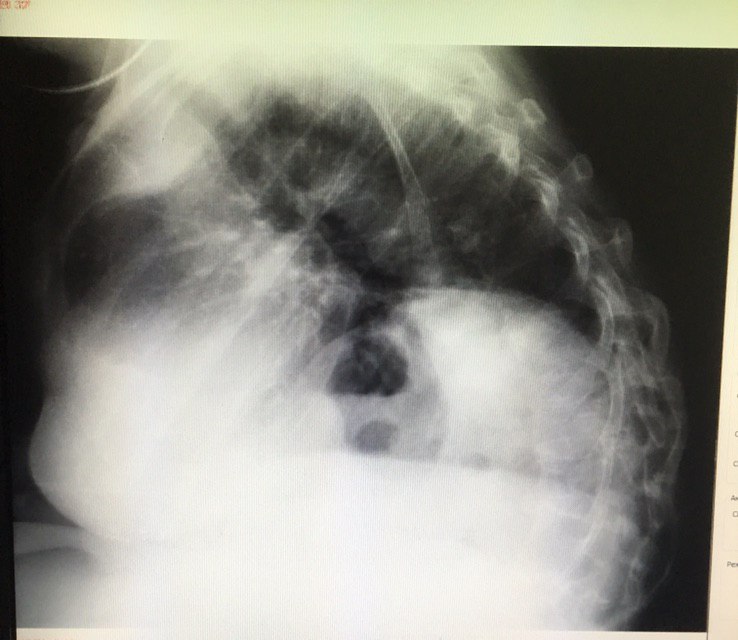

Боковой сделали. Подскажите как описать

Доброе утро.Не подскажите,что может быть?